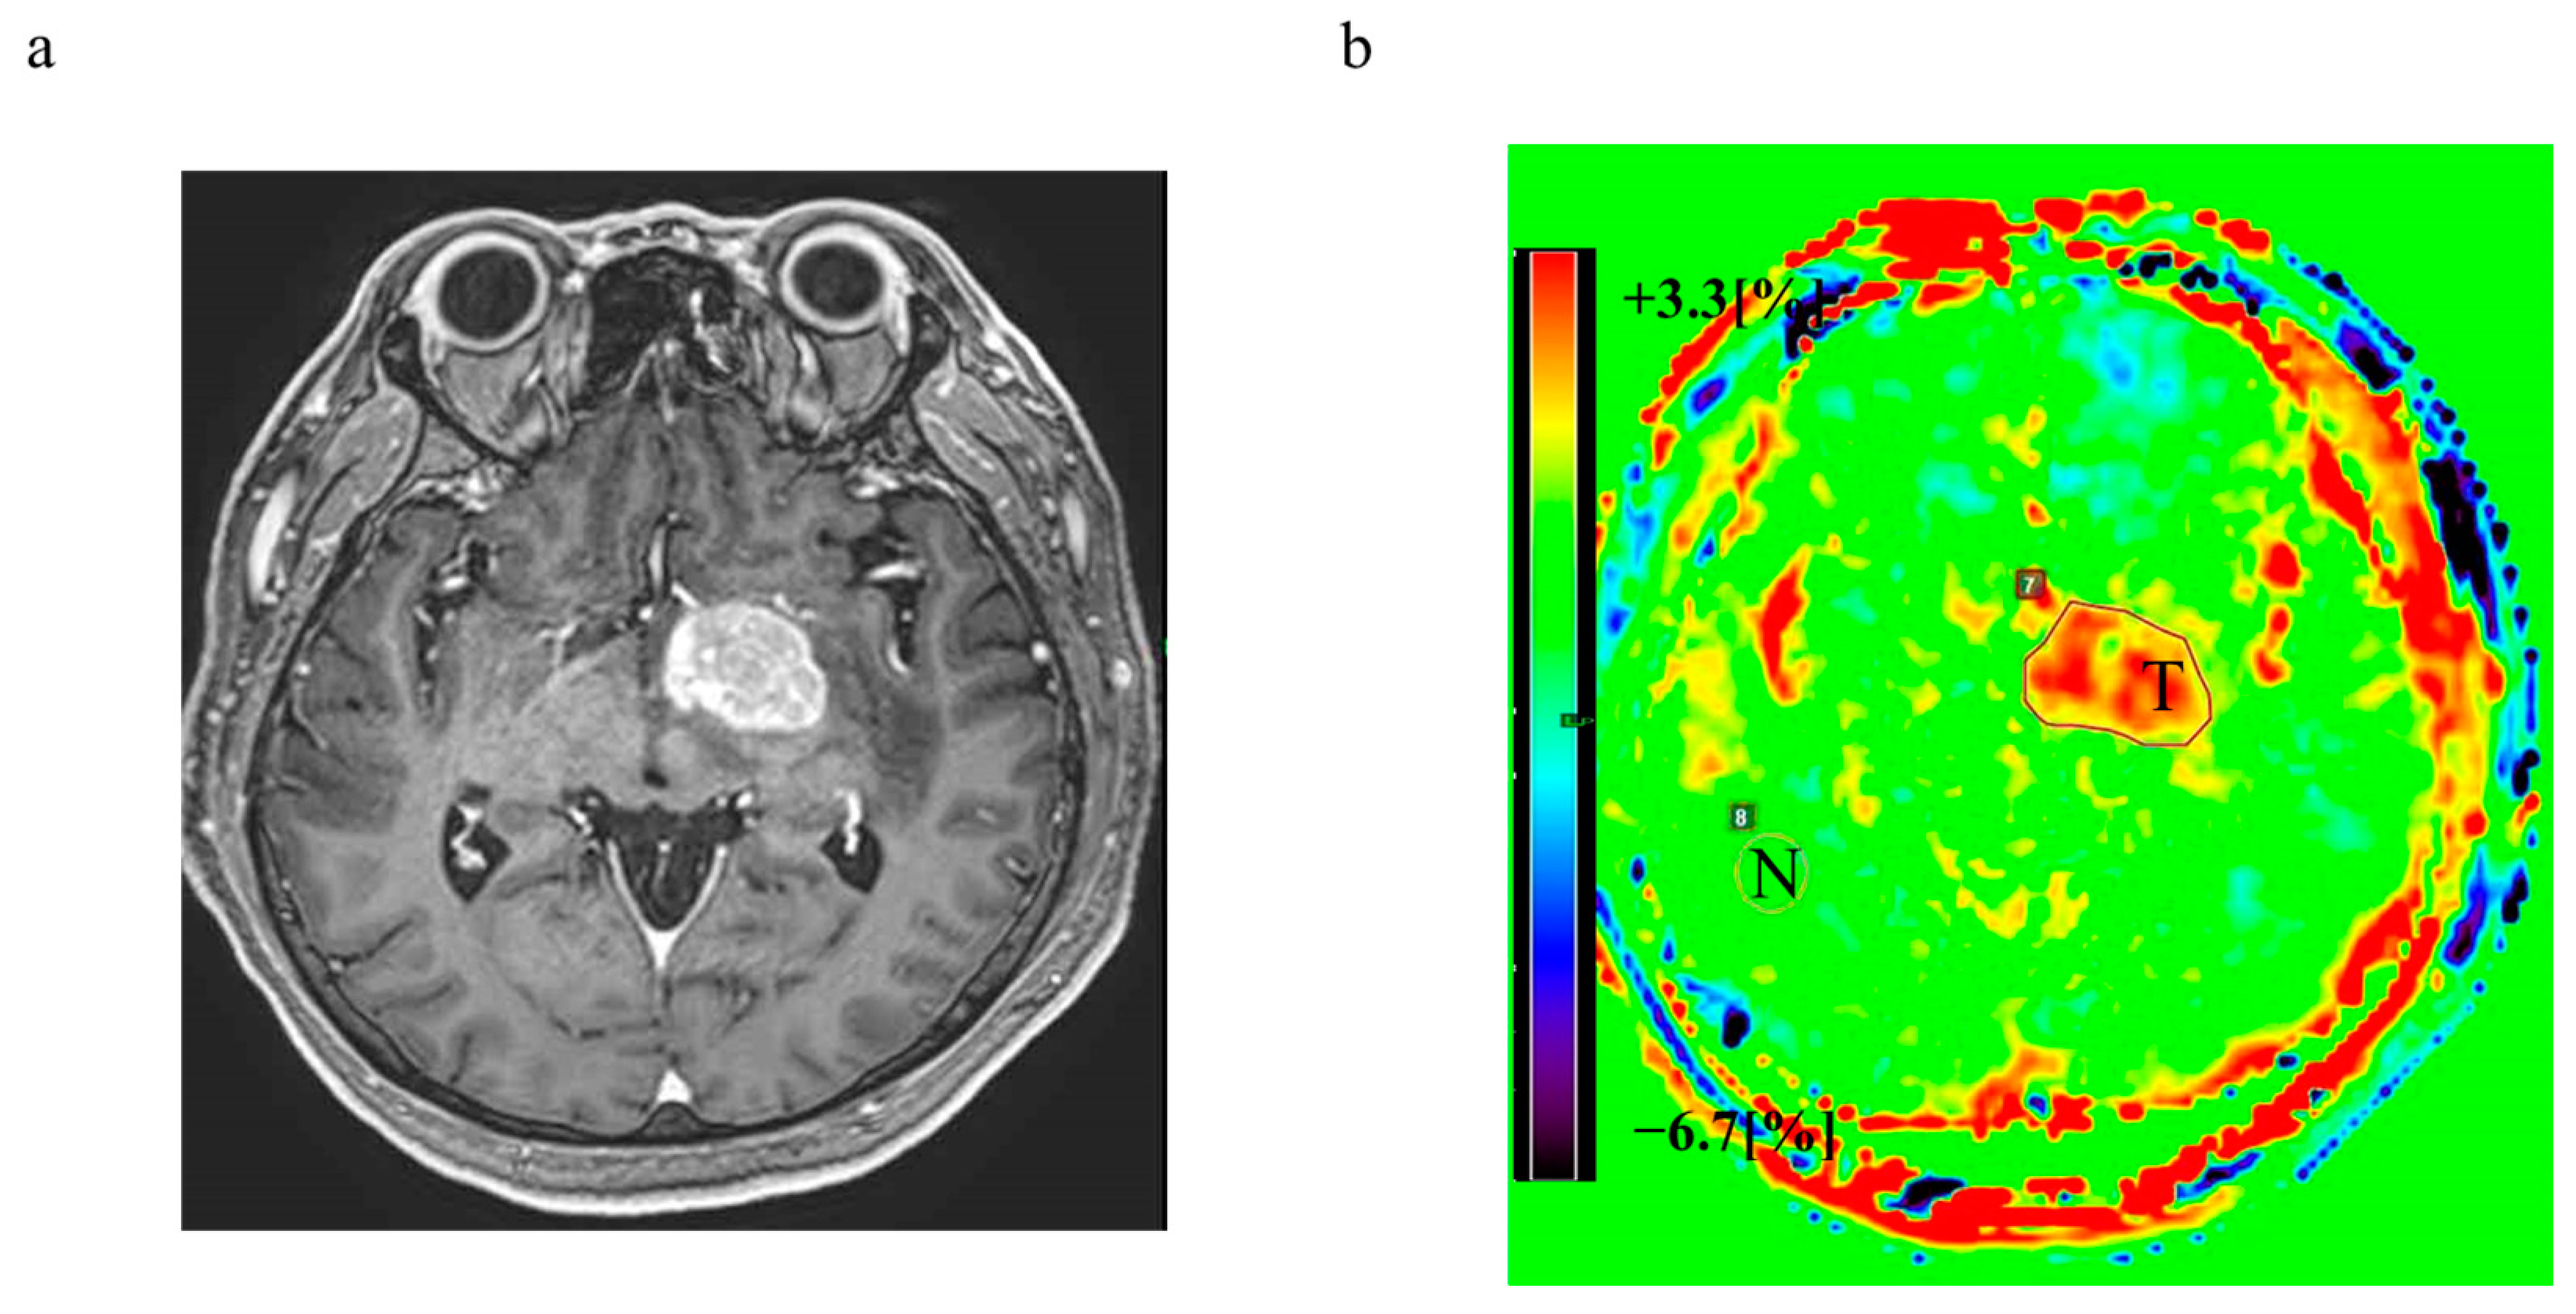

3.6. Representative Cases